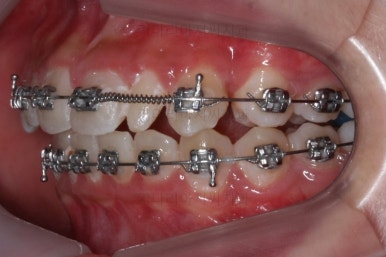

우선 현재 상태에서는 사이즈를 크게 하지 못하기 때문에 왜소치 좌우로 틈새를 만들어주기로 했습니다.

왜소치 좌우로 틈을 일부러 만든 상태입니다.

그 후에 임시 개념으로 사이즈를 크게 만들어 줬어요.

사이즈를 크게 한 뒤에도 약간의 틈이 남아서 다시 틈을 줄여주는 과정을 진행했어요.